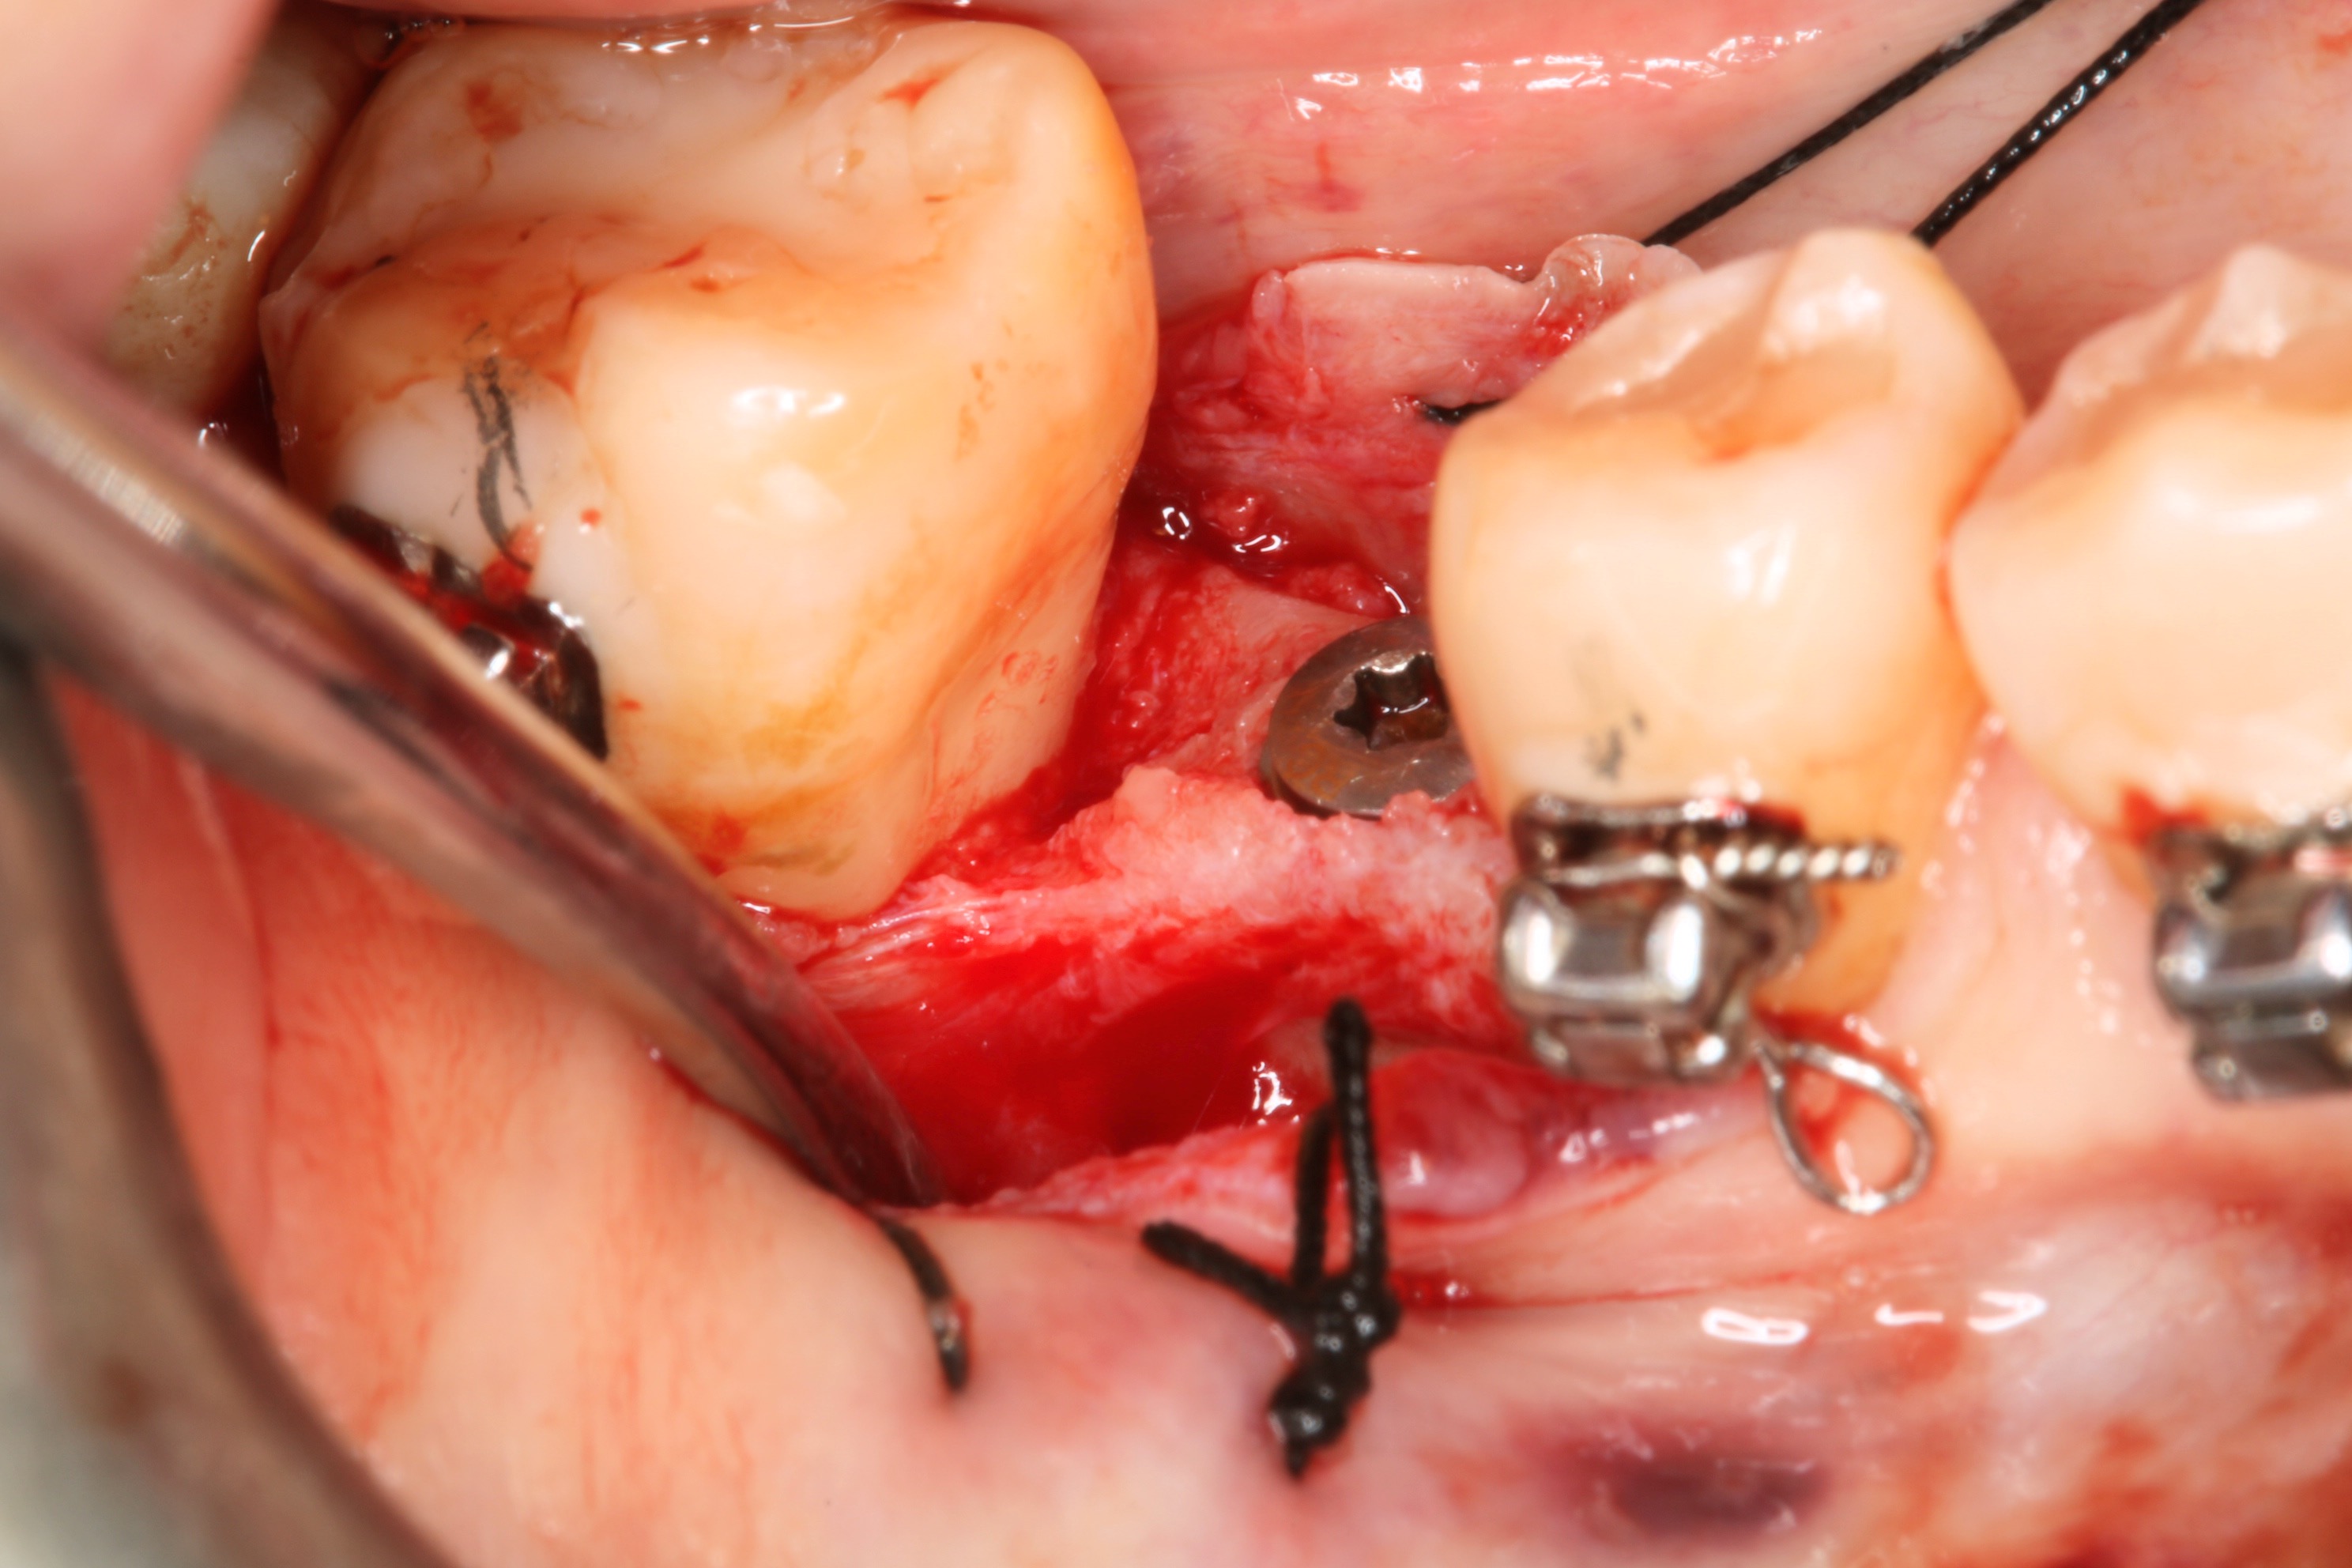

●第十一章垂直補骨,前一版的作者Massimo Simion,改成了Istvan Urban,果如我2016年判斷的,Istvan Urban已成為垂直補骨的接班人,連主編Buser也這麼認為(笑)。這邊寫的是簡易版,若朋友有興趣詳細的垂直補骨,直接看Urban寫的兩本垂直補骨書即可,我這邊也有第二本Vertical 2心得。但是十一章關於頰側與舌側的皮瓣鬆弛,寫得簡潔扼要,值得詳讀。